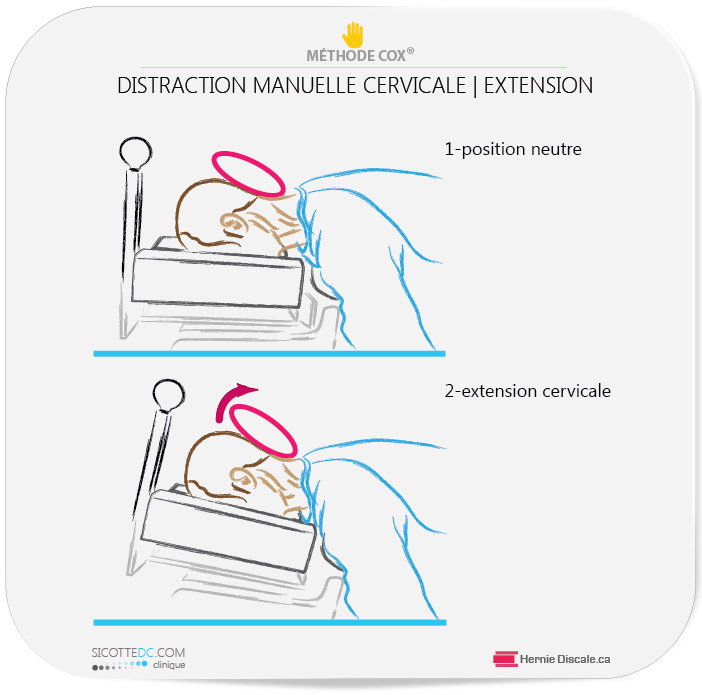

L’EXTENSION CERVICALE ET LA MÉTHODE COX® | TRAITEMENT

L’arthrose cervicale a pour effet de diminuer l’extension cervicale (la tête vers l’arrière). Chez les patients qui ne manifestent pas de signe neurologique, la première étape est d’améliorer l’extension cervicale. Le mouvement de la tête vers l’arrière est essentiel.

Après l’historique, l’examen physique et la radiographie, le clinicien applique l’extension nécessaire adéquate afin de faire cheminer le patient vers une amélioration de son état.

L’augmentation de l’amplitude de mouvement inhibe la douleur chez les patients qui souffrent d’arthrose cervicale. La méthode est extrêmement douce et sans mouvements rapides.

[ Recherche : Intradiscal Pressure Changes during Manual Cervical Distraction: A Cadaveric Study : (Les variations de pression intradiscale lors des distractions cervicales manuelles : une étude cadavérique. 2013)]